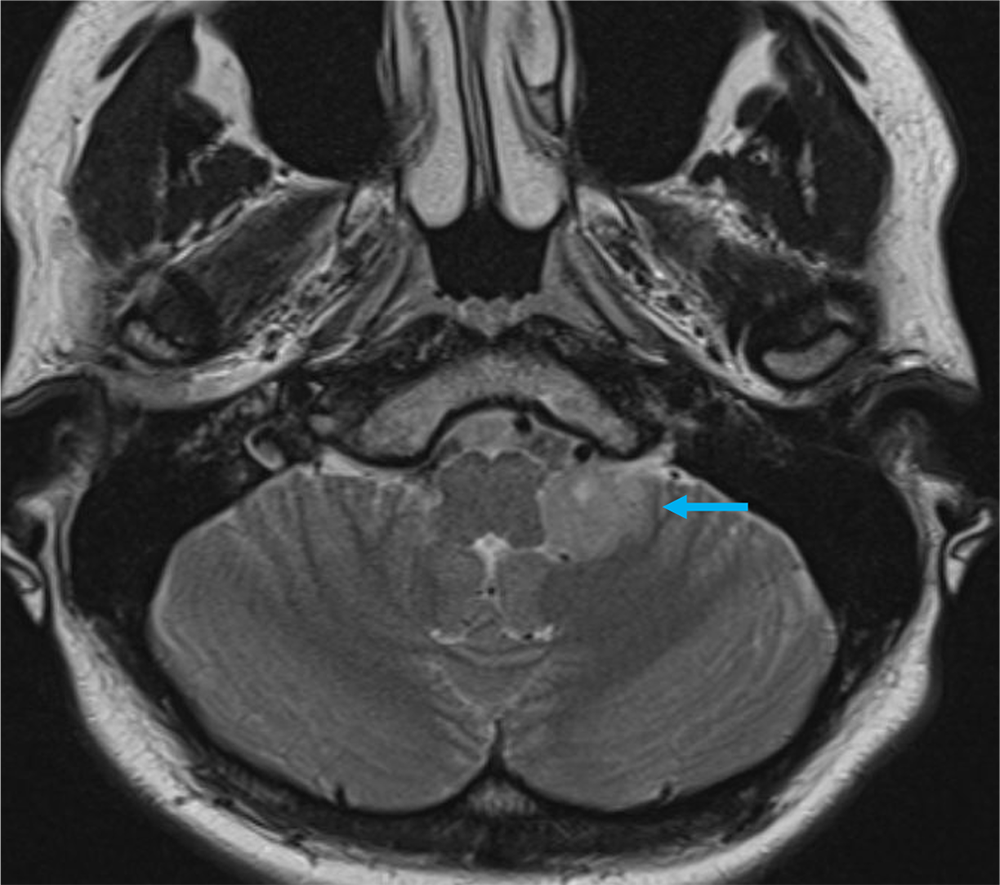

2か月前から頭重感および嘔気が持続しており、他院の単純CTにて左小脳腫瘍が疑われた。当院紹介となり、造影MRIが撮影された。

本症例では左小脳延髄角部に嚢胞成分を伴う腫瘍が存在し、左下位脳神経からの発生、もしくは小脳実質内腫瘍の鑑別が重要であった。前者であれば神経鞘腫、後者であればpilocytic astrocytomaの可能性が高くなる。3Dの脂肪抑制T1強調画像を撮影し、小脳実質内の可能性が高く、pilocytic astrocytomaを上位に考えた。手術が施行され、無事に完全摘出され上記の診断となった。

当該疾患の診断における造影MRIの役割

小脳腫瘍の鑑別において、造影MRIは必須である。本症例のように若年者の小脳実質内腫瘍の場合、特に血管芽腫との区別が重要となる。血管芽腫も嚢胞成分を伴う腫瘤を呈することが多いが、充実成分は強い造影効果を呈する。本症例は血管芽腫を疑うような強い造影効果とは言えず、pilocytic astrocytomaを疑うことが可能であった。